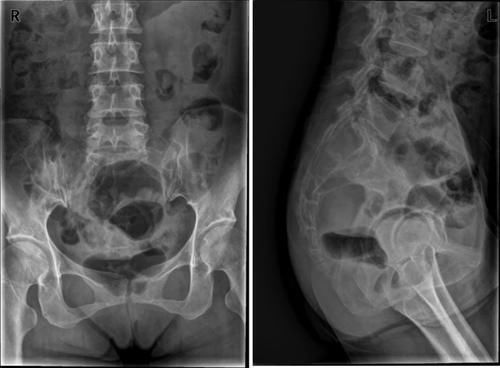

Case14:M,6y;双侧髋部疼痛1月余,加重伴不能行走半月。

文章插图